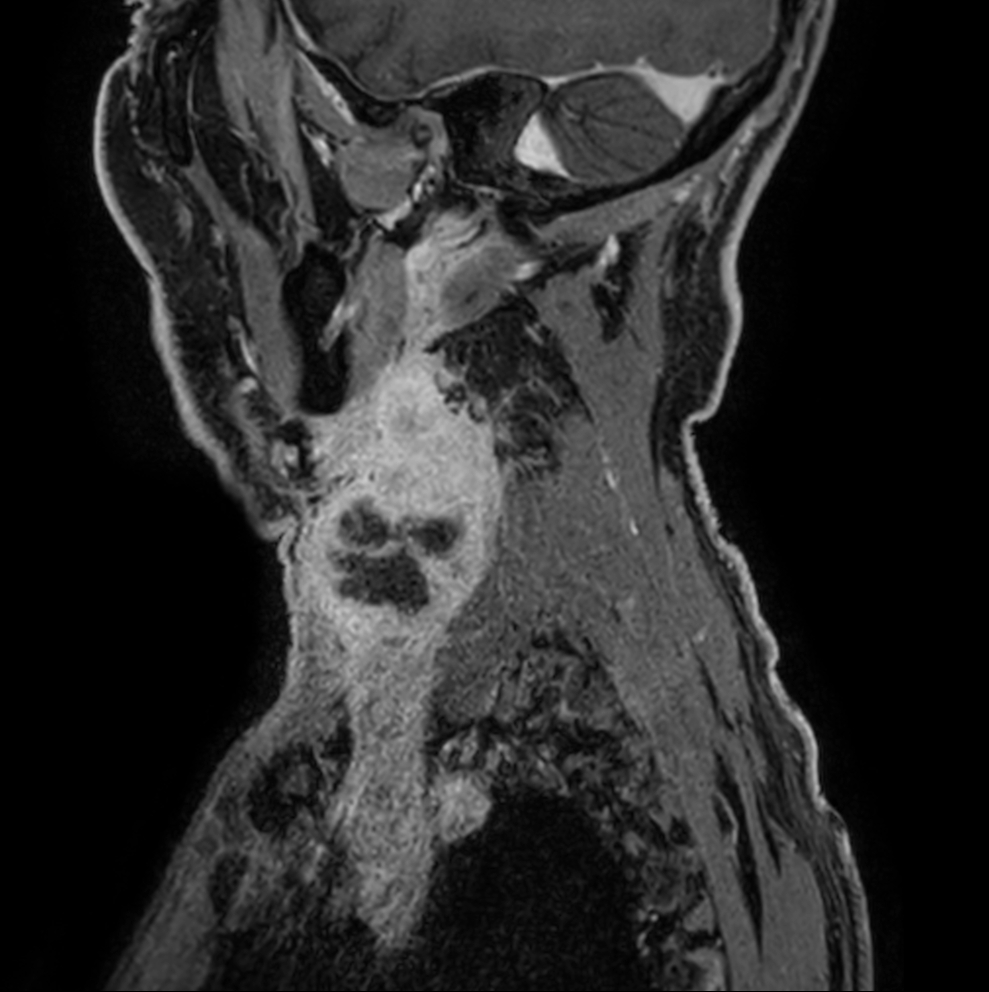

Sagittal T1w mDIXON XD - post-gado